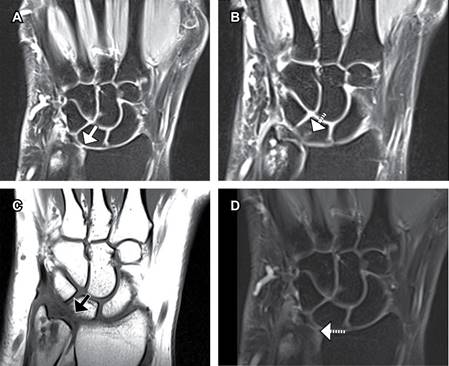

Luego de estudios radiológicos, se observa una varianza cubital neutral, la epífisis distal y apófisis estiloides cubital presentan cambios quísticos erosivos subcondrales con edema medular reactivo de distribución difusa, sin fracturas o fisuras, siguiendo el eje de la superficie articular. Imagen similar, pero en menor grado en el borde proximal dorsal del semilunar, leve edema difuso del fibrocartílago triangular, sin desgarro ni desinserción (Figura 1).

Figura 1: Imágenes de resonancia magnética de la muñeca derecha. A) Imagen coronal potenciada en densidad de protones con fat sat, se muestra (flecha blanca) perforación central de FCT. B) Imagen coronal potenciada en densidad de protones con fat sat, se muestra (flecha blanca discontinua) erosión condral de la porción cubital semilunar. C) Imagen coronal potenciada en T1, se muestra (flecha negra discontinua) erosión condral de la porción cubital del semilunar. D) Imagen coronal potenciada en densidad de protones con fat sat, se muestra (flecha blanca discontinua) comunicación entre las articulaciones cubitocarpiana y radiocubital distal.